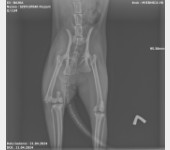

Jest szansa na uratowanie Bajki, ma złamaną prawą tylną łapką i pogruchotaną w kilku miejscach miednicę. Niestety - nasze możliwości finansowe się wyczerpały, życie dość mocno sie ze mną obeszło w ostatnich latach i nie mam generalnie nic. Dziś wydaliśmy wszystkie skromne oszczędności, żeby opłacić leczenie Bajki do tej pory.

Kochani, dzięki Waszym wielkim sercom Bajka dziś pomyślnie przeszła operację - DZIĘKUJEMY ????♥️???? Wielkie brawa dla lekarzy z lecznicy Cztery Łapy w Jeleniej Górze ! Koszt operacji wyniósł 3260 PLN plus każdorazowa wizyta kontrolna 30 PLN plus koszty dodatkowe za miesiąc, tj. wyjęcie śrub, leki, rehabilitacja. Dziś zapłaciłem 3000 PLN, załączam rachunek. Następne załączę przy kolejnych opłatach. Bajka wysyła miaubuźki (. ❛ ᴗ ❛.)